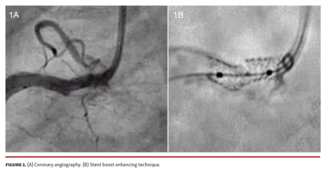

Anunay Gupta, MBBS, MD, DM; Dinkar Bhasin, MBBS, MD, DM; H. S. Isser, MBBS, MD, DM; Gaurav Kumar Arora, MBBS, MD, DM

Uncorrected longitudinal stent deformation increases the risk of major adverse outcomes. Intravascular imaging helps in the recognition of this deformity.

Jessika González D'Gregorio, MD; Agustín Fernandez-Cisnal, MD; Juan Sanchis Forés, MD, PhD; Sergio García-Blas, MD, PhD

The Synergy Megatron stent confers enhanced axial and radial forces, which makes it an ideal choice for ostial and calcified lesions. However, in this case, the stent fractured. We describe the management of this complication.